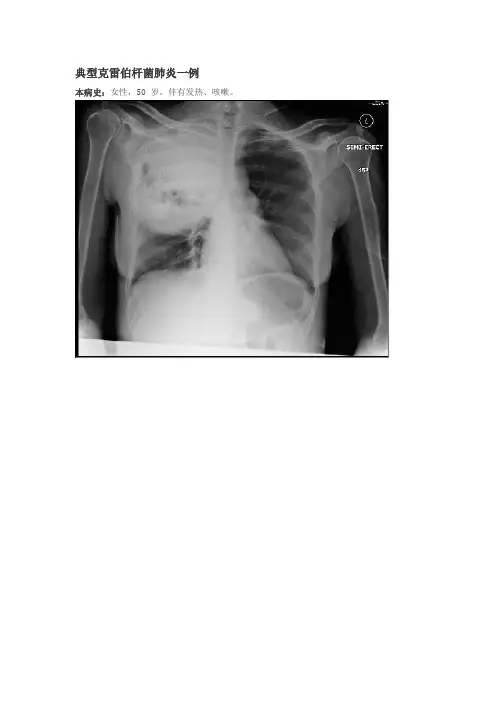

典型克雷伯杆菌肺炎一例本病史:女性,50 岁,伴有发热、咳嗽。

诊断:克雷伯杆菌肺炎案例要点克雷伯杆菌肺炎是一种细菌感染,通常会影响长期嗜酒者和体弱者。

大片实变导致肺叶扩张和裂缝增宽是其特征性影像学表现。

这些表现并不是仅见于克雷伯杆菌肺炎,在其他病因的肺炎也可能会见到。

胸片典型的影像学特征包括大量分泌物引起肺叶实变导致裂隙增宽。

右肺上叶是最常见的发病部位。

虽然裂隙的膨出(叶间裂膨出征)已历来相对用于肺炎克雷伯杆菌肺炎的描述,但不是克雷伯杆菌的特异性病征,并且可以更频繁的出现在其它病原体引起的肺炎,如肺炎链球菌、流血嗜血杆菌、金黄色葡萄球菌,也可以在原发性肺恶性肿瘤里见到。